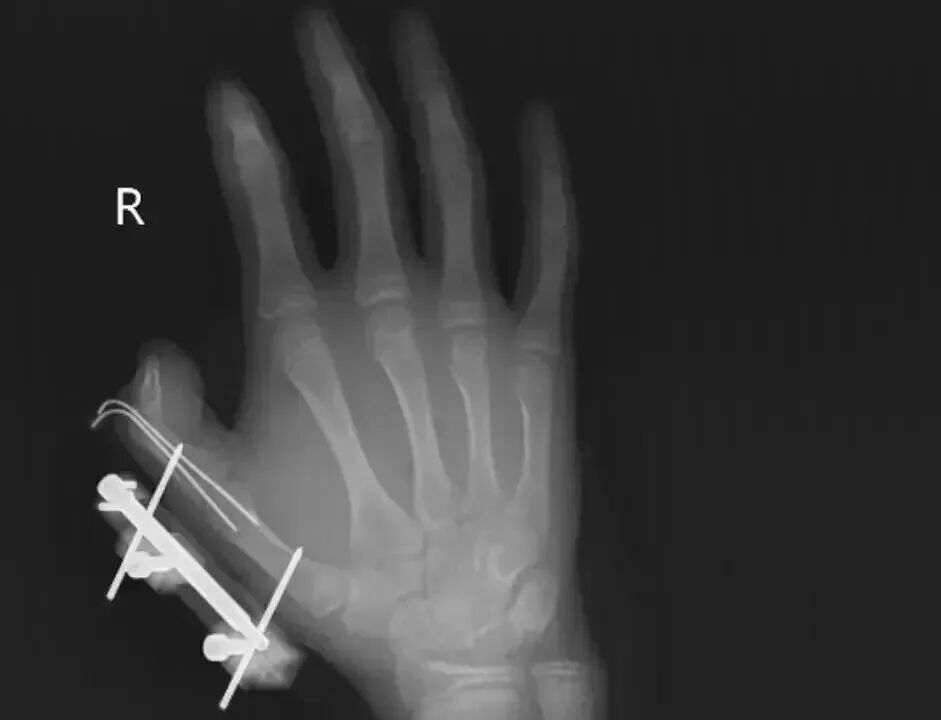

湖南14岁少年维维(化名)在网购冰淇淋的箱子里发现了干冰,便当成玩具捏在手里反复摇晃。突然,干冰发生爆炸,维维拇指虎口处被撕开一道约10厘米伤口,深可见骨,还伴随着拇指骨折、关节脱位,整个拇指完全失去知觉。